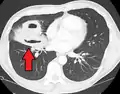

| Computed tomography (CT) scan of chest showing bilateral pneumonia with abscesses, effusions, and caverns. 37-year-old male. | |

Pulmonary abscess on CT scan